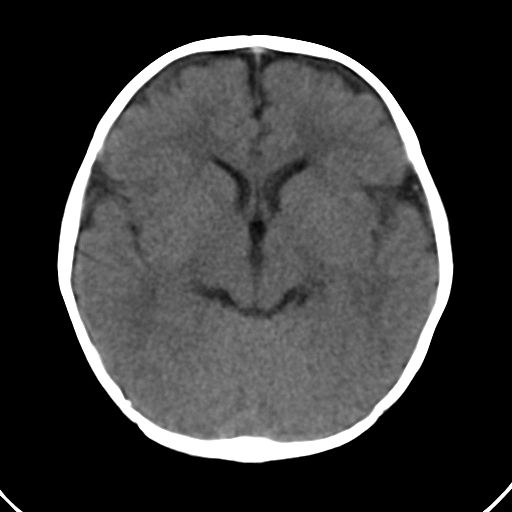

男,10月,足月剖腹产,无缺氧病史,当时评分均正常,学走路时脚后跟不着地!

小孩子片子,看得少,请各位老师看看有问题没?

未见明显异常。

外部性脑积水

考虑外部性脑积水

轻度脑外脑积水表现.